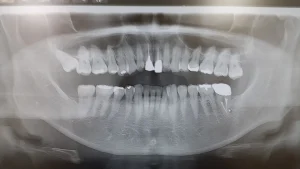

そのためにCTを術前に撮影する場合もありますので、次回は「CT」についてお話します。